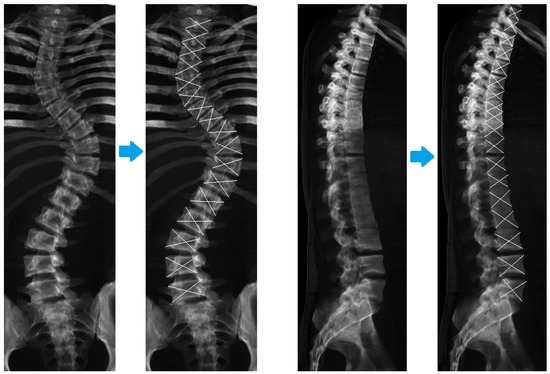

Improvement in Scoliosis Top View: Evaluation of Vertebrae Localization in Scoliotic Spine-Spine Axial Presentation